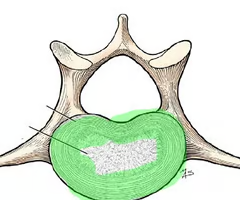

Herniated (slipped) disc

Occurs when spongy nucleus pulposus protruded thru a rupture in annulus fibrosus and presses on the spinal cord or spinal nerves.

Nucleus pulposus

Annulus fibrosus

Herniated (slipped) disc